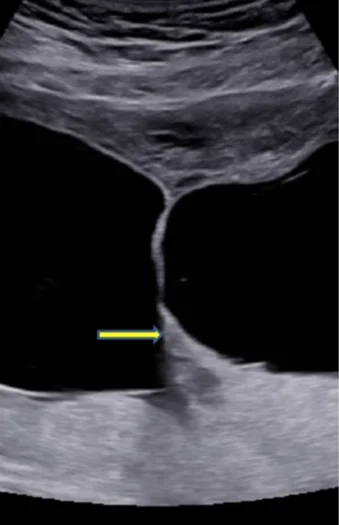

Bánh nhau - túi ối trong song thai (Chorionicity- Amnionicity)

Song thai một nhau - hai ối (Monochorionic Diamniotic Twins - MCDA)